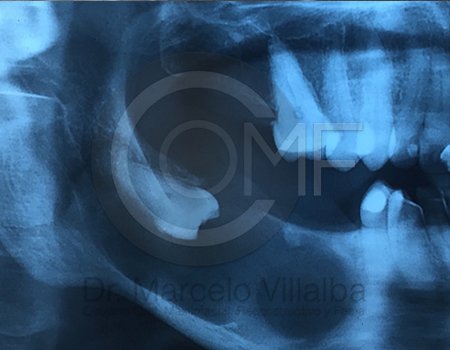

Contenido Sensible y Gráfico

Si usted no pertenece al área de la salud, las imágenes pueden ser muy explícitas.